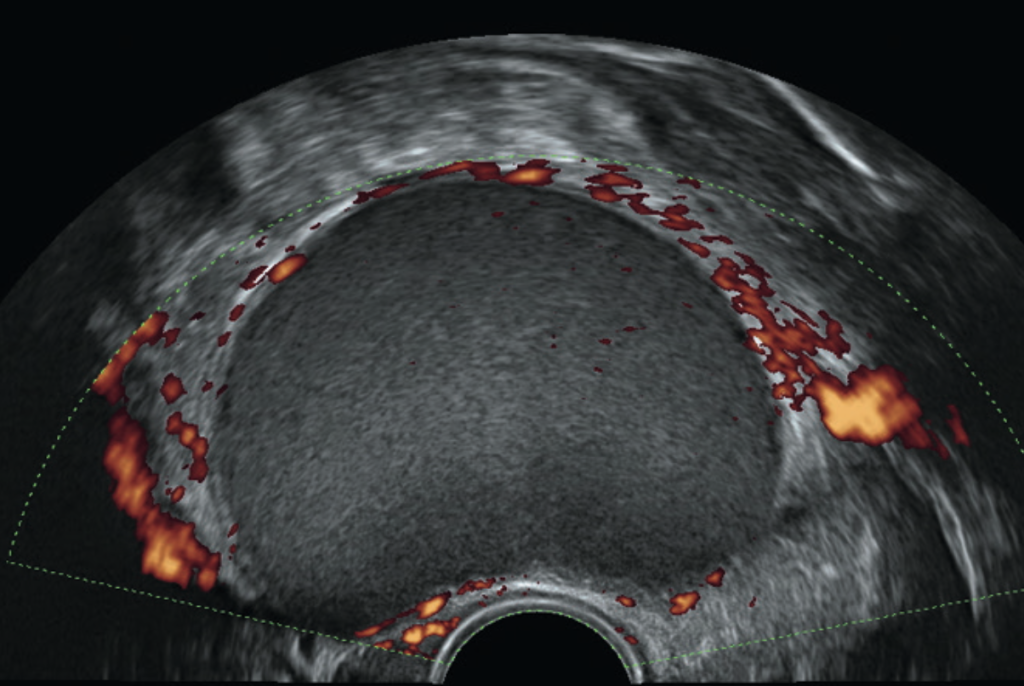

L’échographie pelvienne réalisée par voie vaginale est le premier examen à effectuer lorsqu’on soupçonne une endométriose.

Il s’agit d’un examen spécialisé devant être effectué par un radiologue référent dans cette pathologie et à l’aide d’un matériel de qualité. Lorsqu’elle est effectuée par un radiologue formé dans le dépistage de l’endométriose et expérimenté, l’échographie permet dans la plupart des cas de dépister les atteintes ovariennes, rétro-utérines, digestives et vésicales.

Elle est réalisée par voie vaginale (à l’exception bien sûr des patientes vierges) à l’aide d’une sonde soigneusement désinfectée avant chaque examen, ne nécessite pas de préparation particulière et dure une quinzaine de minutes. Il s’agit d’un examen indolore dans la majorité des cas.